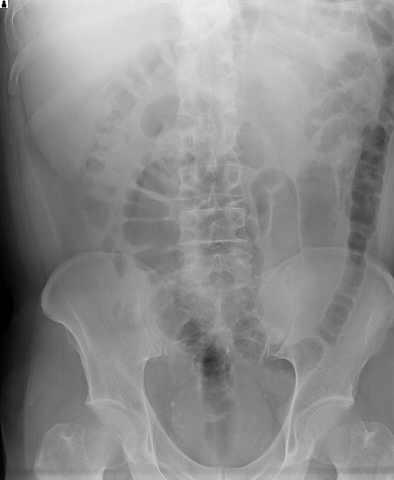

X-P

ひどい胃腸炎

説明